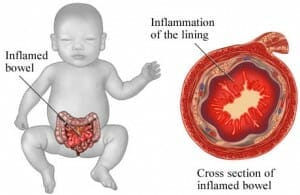

Enterocolitis

Enterocolitis is een infectieziekte die veroorzaakt wor...